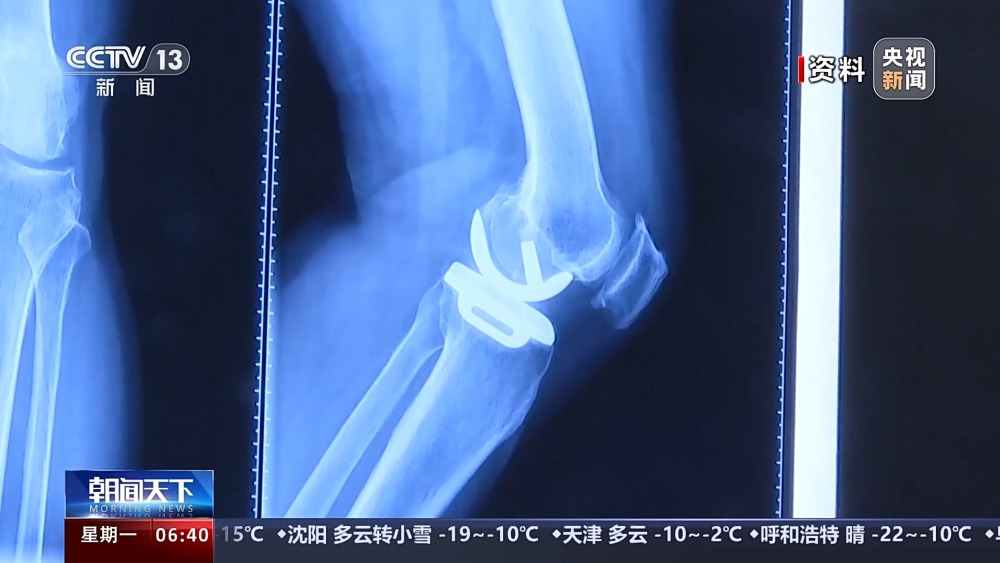

目前,我國有超過1億人患有骨關(guān)節(jié)炎,65歲以上人群中,骨關(guān)節(jié)炎發(fā)病率接近50%。以前,嚴重骨關(guān)節(jié)炎患者主要通過膝關(guān)節(jié)置換手術(shù)來維持行走等基本功能。膝關(guān)節(jié)置換手術(shù)存在術(shù)后關(guān)節(jié)僵硬、長期疼痛等問題。保膝治療包括藥物、理療等保守治療,以及手術(shù)治療。

保膝手術(shù)主要包括截骨術(shù)和單髁置換術(shù),其中截骨術(shù)在解決患者疼痛癥狀的同時,阻止下肢異常應力對膝關(guān)節(jié)的進一步損傷,膝關(guān)節(jié)內(nèi)所有軟骨韌帶、半月板都得到了保留。內(nèi)側(cè)單髁置換術(shù),使膝關(guān)節(jié)外側(cè)健康的軟骨和半月板得到了保留,膝關(guān)節(jié)內(nèi)外側(cè)的韌帶維持原有狀態(tài),患者康復后,擁有正常的膝關(guān)節(jié)功能。